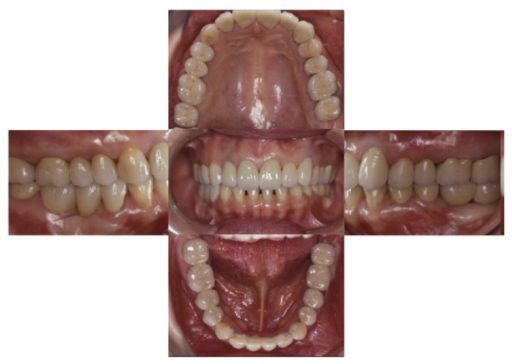

下顎臼歯部が欠損した患者さんのインプラント治療の症例②(うえだ歯科)

症例詳細

| 主訴 | 全顎治療希望、下の奥の歯が無いので全く噛めない。綺麗で噛めるようになりたい |

| 治療内容 | 下顎臼歯部欠損放置のため、臼歯部においてスペースがないため、全顎治療を行い咬合再構成を行う。 早期においてインプラント治療、咬合関係を模索した後、全顎にわたりセラミックによる補綴治療、その後メインテナンスに移行 |

| 治療費 | 5,410,000円(税込)(インプラントすべて含む) |

| 治療期間 | 1年8ヶ月 |

| 治療回数 | 80回 |

| 想定されたリスク | 食いしばり(パラファンクション)によるセラミックの破折、歯の破折 |